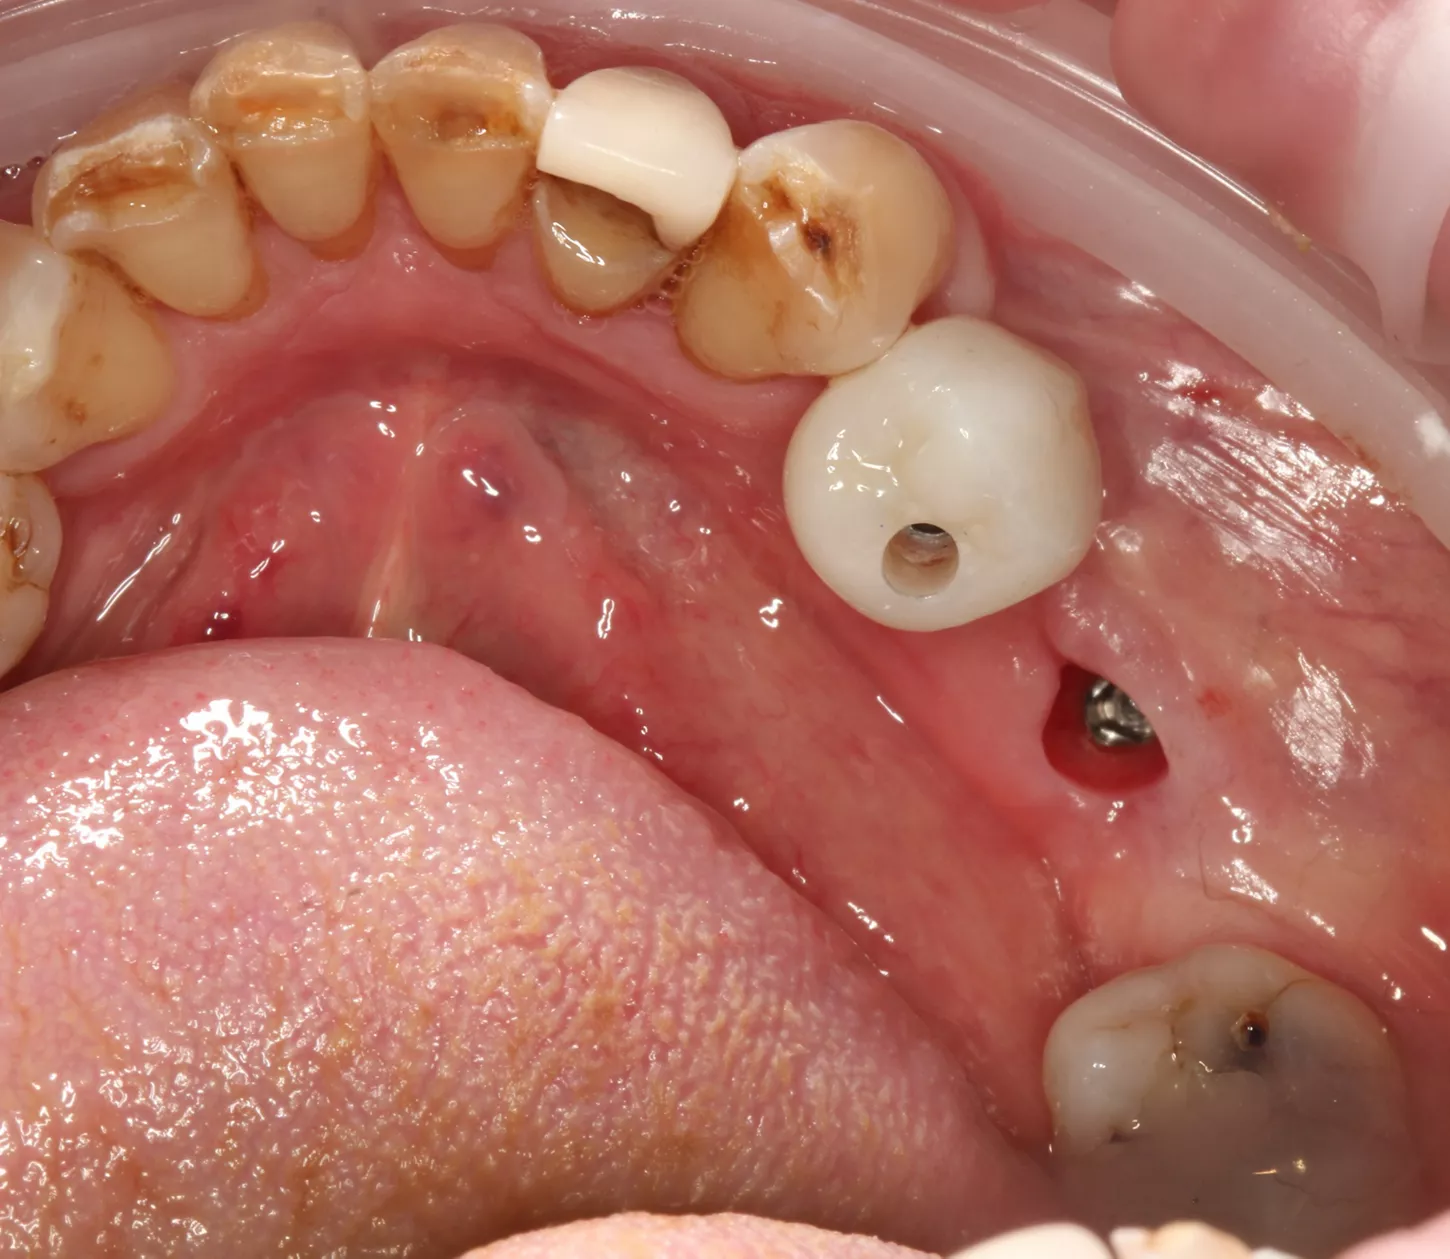

For the maxillary single‑tooth implant, a fully digital guided workflow was used, allowing a flapless approach. Soft‑tissue access was achieved with a tissue punch through the surgical guide [5], followed by osteotomy preparation using the Axiom® X3 drilling protocol. The implant achieved high primary stability (≈50 N·cm), enabling immediate placement of a HealFit® SH without suturing.

11a. 11b. 11c. 11d. Flapless guided placement of the maxillary implant with tissue‑punch access, Axiom X3 osteotomy, and immediate HealFit® SH placement without sutures.

11a

11b

11c

11d